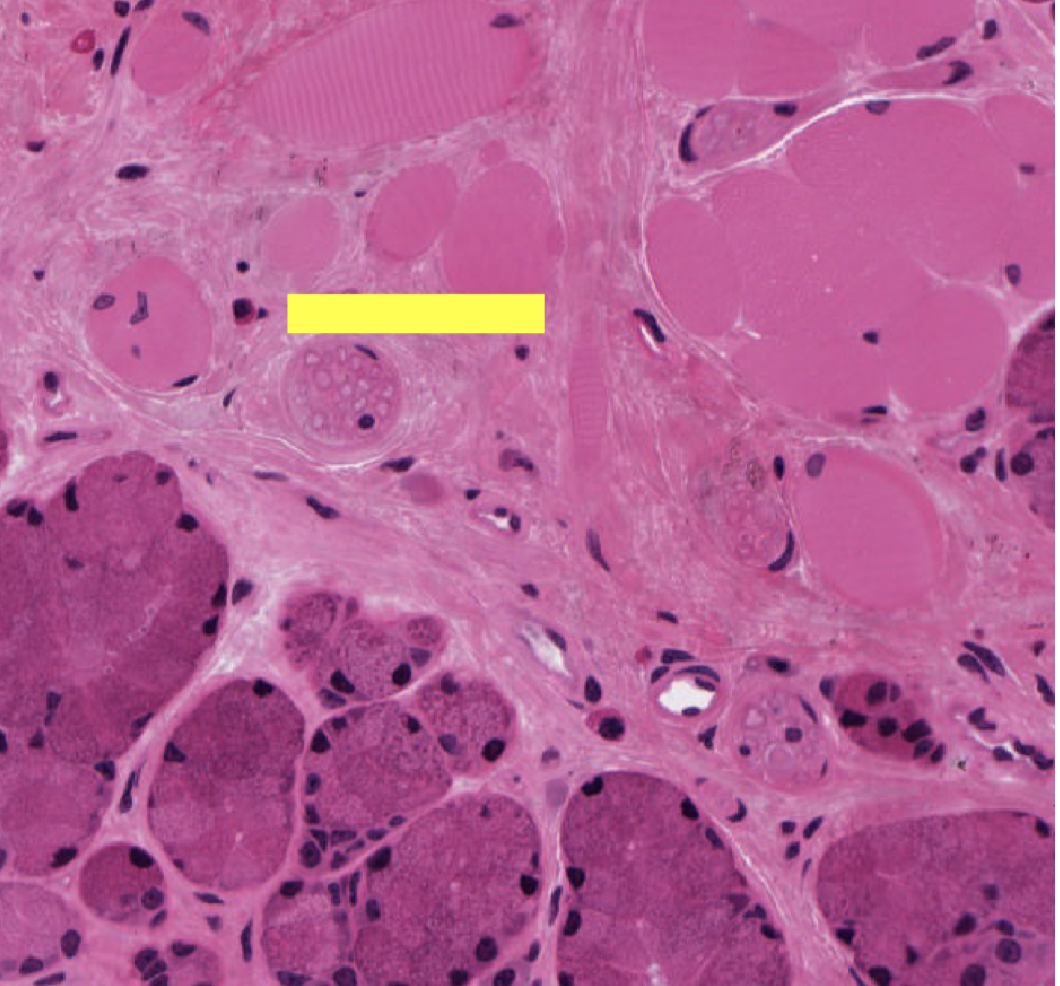

where in the body are we

where in body